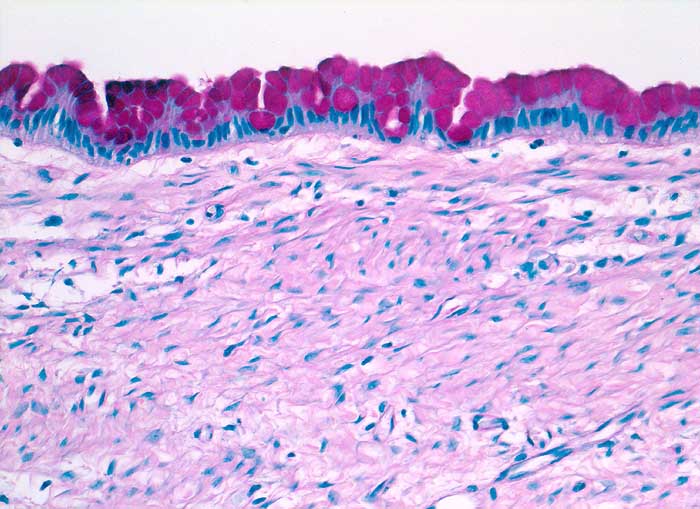

Muzinöses Zystadenom

benigner Tumor

Ovar

Die Zyste ist ausgekleidet von schleimbildenden Zylinderzellen ohne Atypie.

Schleim++

"Ovarialzyste" (gross) Dm 20cm.

Da hochdifferenzierte muzinöse Karzinome bisweilen kaum Atypien aufweisen, ist die sorgfältige Untersuchung des Operationspräparates notwendig (mindestens 1 Block pro cm Tumordurchmesser)

200